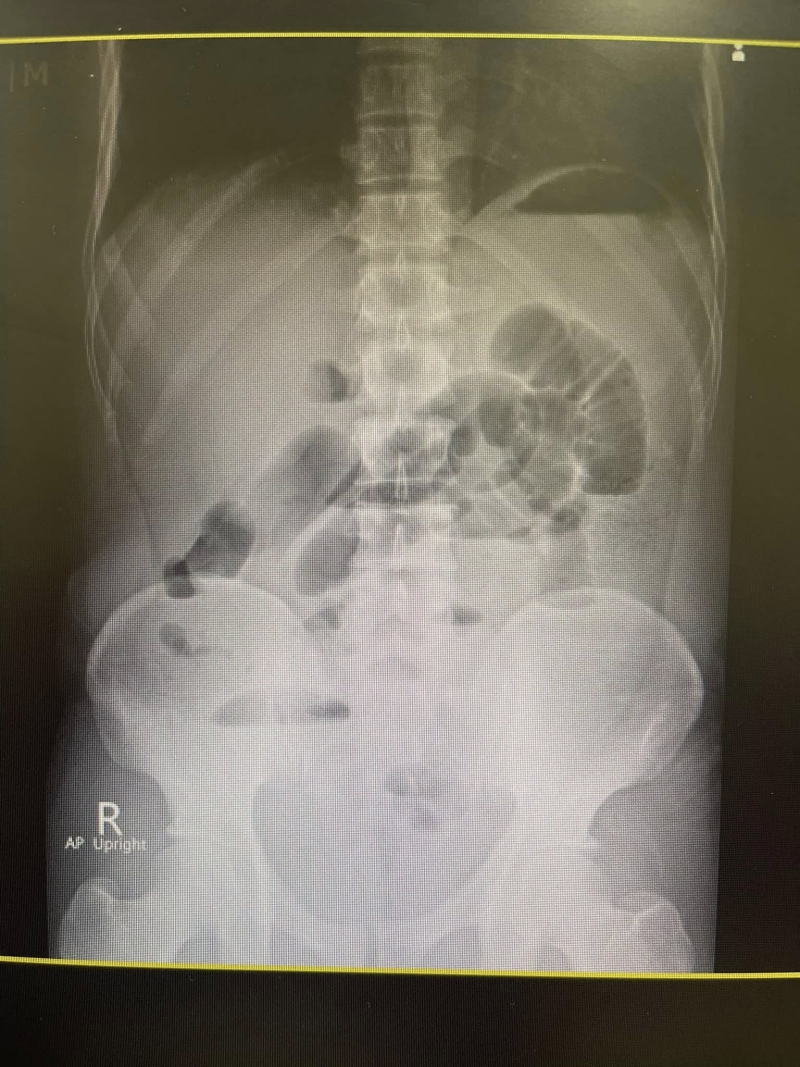

คนไข้อายุสี่สิบเศษ กินน้ำท่อม ทุกวันมา 4-5 ปี ปวดท้องจึงมาโรงพยาบาล ผมคลำแล้วก็พบว่าท้องอืดๆ ให้ไปเอ็กซเรย์ กลับมาภาพสวยเหมือนในตำรา พบว่ามีภาวะลำไส้อุดตัน จึงให้นอนโรงพยาบาลใส่สายยาง NG tube เข้ากระเพาะต่อกับเครื่องดูดลมออกจากกระเพาะ ถ้าดีขึ้นลำไส้คลายตัวก็โล่งไป ถ้าไม่ดีก็ต้องส่งไปผ่าตัด

รายนี้ยืนยันกินแต่น้ำท่อม ไม่ได้กินใบท่อมสดๆ (ปกติลำไส้อุดตันมักพบในคนกินใบกระท่อมสดๆ) ไม่เคยมีประวัติผ่าตัดใดๆ